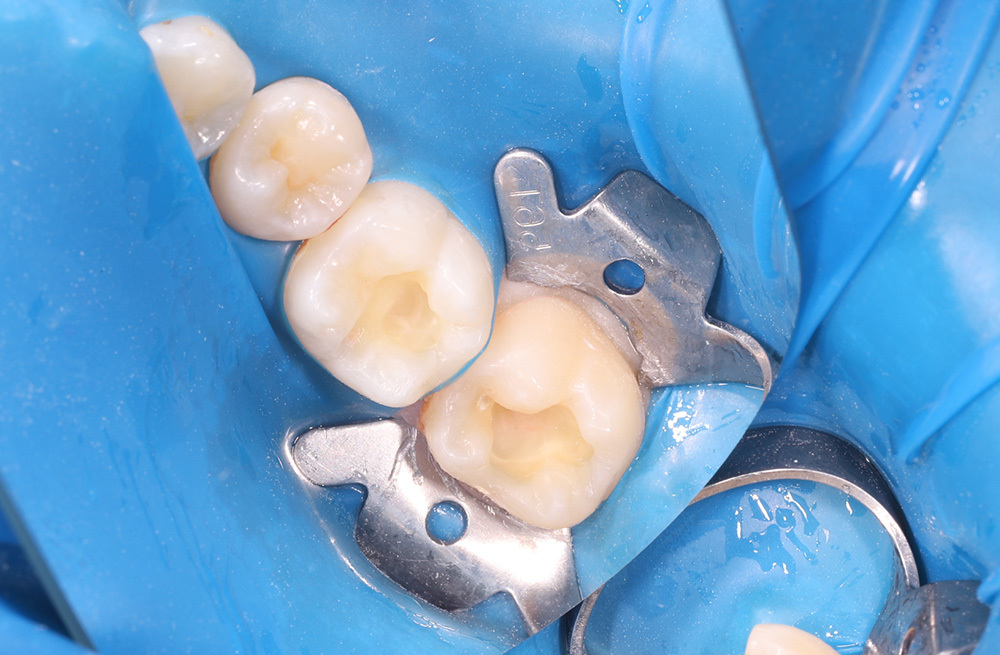

Композитное восстановление жевательной поверхности после удаления межзубного кариеса

Лечение скрытого кариеса на контактной поверхности с установкой композитной пломбы